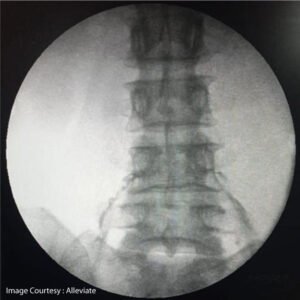

Fluroscopy Guided Transforaminal Epidural Injection